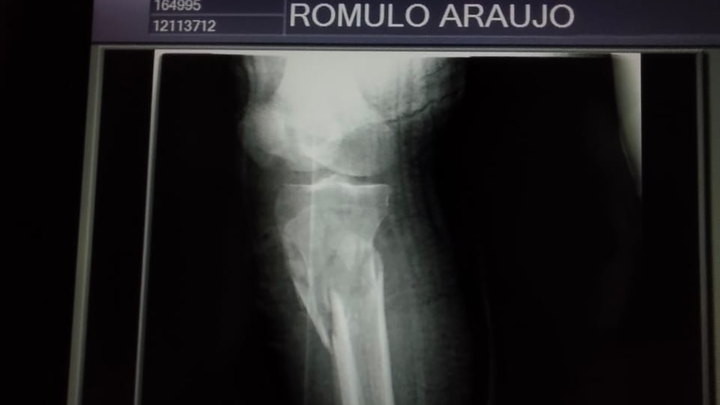

Fractura de fémur

Fractura de tibia

Rodilla gravemente lesionada

Problemas en la cadera

Necesita una cirugía urgente para reconstruir su pierna y evitar complicaciones permanentes. Sin esta operación, corre el riesgo de perder movilidad y no poder volver a caminar con normalidad.